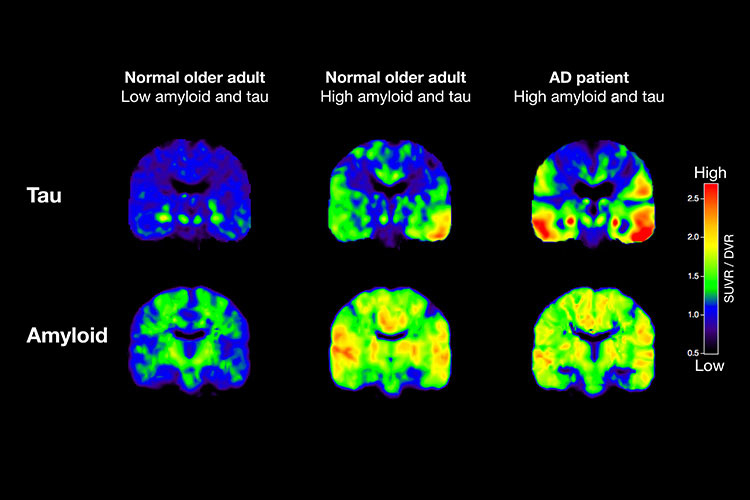

Η πρωτεΐνη ταυ και το βήτα αμυλοειδές μπορούν να ανιχνευτούν με τομογραφία PET, μια ακριβή και συχνά μη διαθέσιμη εξέταση (Michael Schöll)

Η παρουσία των παθολογικών πρωτεϊνών επιβεβαιώθηκε με τομογραφία PET και εξετάσεις στο εγκεφαλονωτιαίο υγρό, τις μόνες εξετάσεις που θεωρούνται αξιόπιστες για τη διάγνωση της Αλτσχάιμερ πέρα από τη νεκροψία. Και οι δύο είναι ακριβές και δεν χρησιμοποιούνται ευρέως.